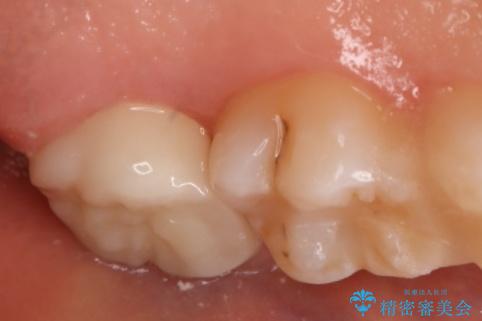

- 左上7番の虫歯治療を主訴に来院された患者様です。

虫歯の範囲が広かったので切削量・形態を考慮し、セラミッククラウンでの治療を計画しました。

虫歯の範囲が広い場合、大きく削る必要があるので部分的に詰めるインレーではなく、クラウンでの治療になることがあります。